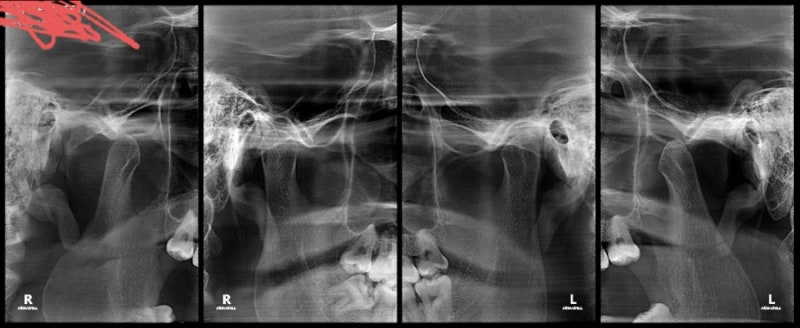

<주제 1:생활 습관>편도 비대를 관리하는 예방하기 위해서 건강한 생활 습관을 유지해야 합니다.이 includes음식 습관 개선, 흡연 중단, 충분한 수면, 규칙적인 운동 등입니다.이들의 생활 습관은 편도선 비대의 발생과 진행에 영향을 줄 수 있습니다.<주제 2:관련 자료>편도 비대에 관한 최신 자료와 정보를 찾아볼 일이 중요합니다.의료 웹 사이트, 학술 논문, 환자 지원 그룹 등에서 신뢰할 자료를 찾아 읽어 보세요.이들 데이터는 편도 비대를 이해하고 관리하는데 도움이 됩니다.<주제 3:예후 예측>편도 비대 환자의 예후 예측은 중요한 과제의 1개입니다.의료 전문가들은 환자의 상태와 진행을 예측하고 적절한 치료 계획을 책정하기 위해서 다양한 지표가 검사를 사용합니다.환자 맞춤형 치료 방법을 결정하는데 도움이 됩니다.<주제 4:진단 방법>편도 비대를 진단하기 위해서는 의료 전문가의 진료와 다양한 진단 검사가 필요합니다.이들 검사는 내시경 검사, 초음파, 조직 검사 등이 포함되는 경우가 있습니다.정확한 진단은 적절한 치료 계획을 책정하는 데 중요합니다.이처럼 편도 비대:생활 습관, 관련 자료, 예후 예측, 진단 방법이란 제목 아래, 테마에 따른 내용을 작성했습니다.각 주제는 500글자 이상으로 구성되어 있습니다.마지막으로 내용을 마치겠습니다.